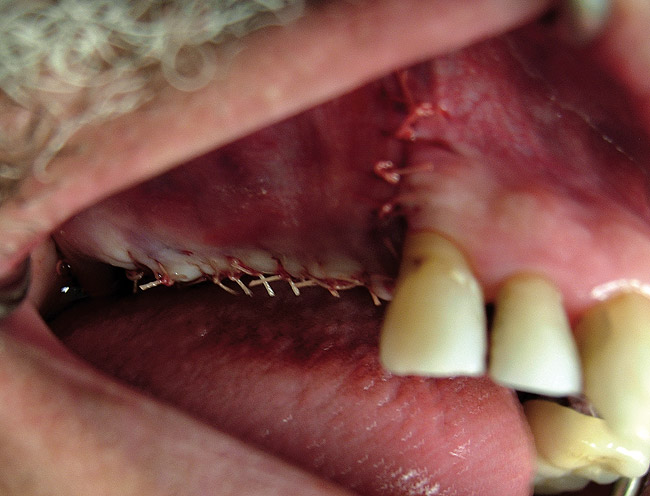

Figure  7  The graft after suturing.

Postsurgical

Drugs that are often prescribed are amoxicillin 500 mg tid or clindamycin 300 mg tid for 10 days, glucocorticoids (dexamethasone 4 mg for 2 days), ibuprofen 600 mg every 4 to 6 hours for pain if needed, and 0.12% chlorhexidine twice daily for 10 days (Figure 7).